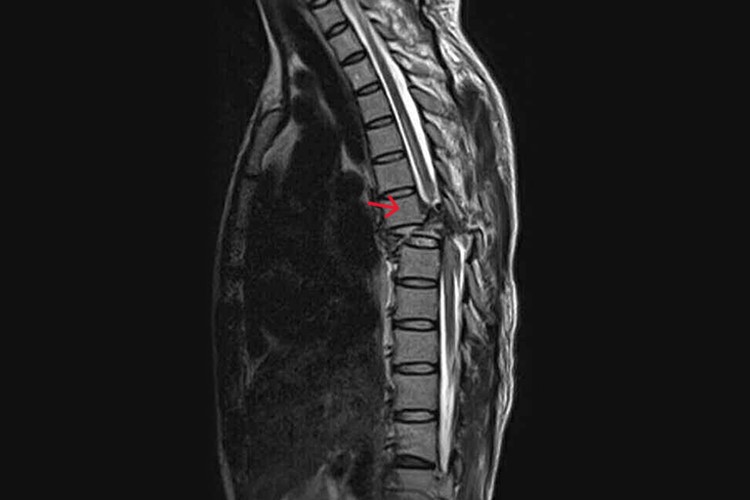

胸椎十二节压缩性骨折恢复正常的时间因人而异,受到多种因素的制约,一般在4-24个月,与骨折压缩程度、神经损伤情况、个体差异等方面有关,患者在治疗和康复过程中应积极配合,以争取良好的预后。

3、严重压缩但神经未损:

- 若骨折压缩严重,但椎管内神经未受损伤,可能需要手术治疗。术后12-16周骨折逐渐愈合,经过4-8个月的康复训练,包括腰背肌锻炼等,可能8-12个月能恢复到接近正常状态。

- 当骨折导致神经受压或损伤时,恢复时间显著延长。手术解除神经压迫后,神经功能的恢复需要较长时间,骨折愈合可能需16-20周。整体恢复正常可能需要1-2年,甚至更长,且部分功能可能难以完全恢复。